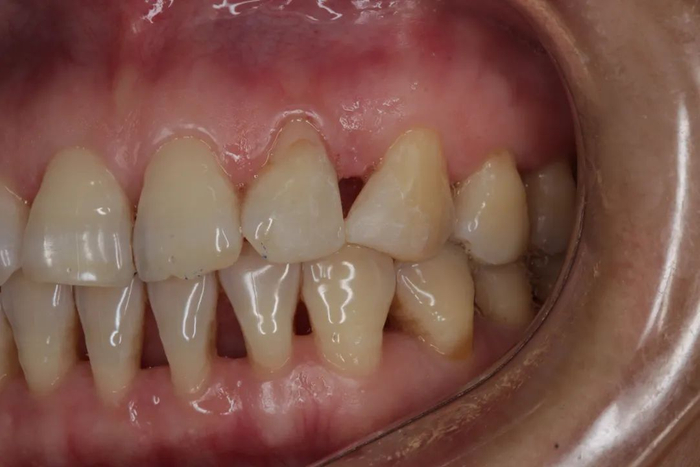

慢慢地,你不在意,牙龈只是有点退缩,然后牙齿缝慢慢显露出来,露出难看的「黑三角」。

由于牙龈退缩,牙齿之间形成了「黑三角」,此时要治疗和改善已经非常困难,